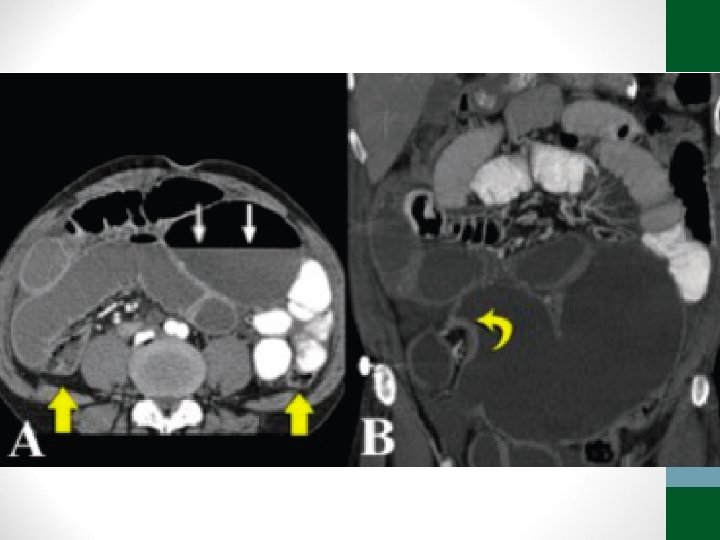

Exames de Imagem • Abdome Agudo Vascular: • Radiografia simples de abdome: decúbito, ortostase e cúpulas diafragmáticas • USG abdome não ajuda! • TC Abdome com contraste EV e VO – angio. TC (fase arterial e portal) é o melhor exame

Abdome Agudo Vascular • 50 a 70% de mortalidade • Causa relevante de óbito em pacientes internados em UTI • Diagnóstico e tratamento precoces (até 6 h do início da dor) aumentam a sobrevida • Requer alto índice de suspeição, pois os sintomas são inespecíficos no início do quadro • Pode ser confundido com quadro de obstrução intestinal

Abdome Agudo Vascular • Etilogia: • Isquemia arterial oclusiva • Embolia (50%) • Trombose (20%) • Isquemia arterial não-oclusiva (25%) • Trombose venosa (5%)

Trombose arterial Embolia arterial Isquemia arterial não-oclusiva Trombose venosa Quadro clínico Dor abdominal difusa intensa, sem irritação peritoneal. Antecedente angina mesentérica Dor abdominal difusa e intensa, sem irritação peritoneal Paciente crítico com ditensão abdominal, febre, leucocitose, sangramento digestivo Dor e distensão abdominal mais insidiosa. Sangramento digestivo comum Intestino acometido Todo delgado e cólon direito Poupa intestino delgado proximal Variável Poupa cólon Doenças associadas DAOC, AVC, FA, ICC dilatada, operação vascular IAM, AA, AVC, prévia procedimento endovascular ICC grave, uso DVA, Trombofilias, PV, PO cirurgia cardíaca, cirrose hepática, cocaína, ergot neoplasias, ACOH Tratamento Revascularização da AMS ou fibrinólise. Se necrose: ressecção e reabordagens Infusão intra-arterial de vasodilatadores (papaverina). Se necrose: ressecção e reabordagens Embolectomia da AMS ou fibrinólise. Se necrose: ressecção e reabordagens Anticoagulação plena. Se necrose: ressecção e reabordagens